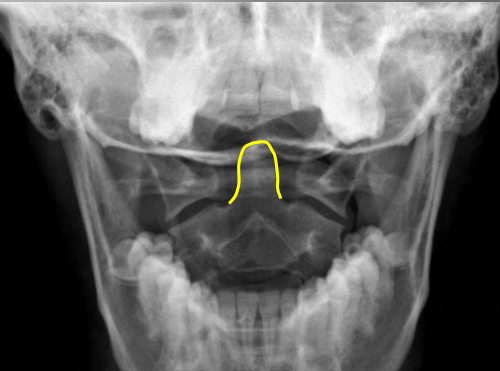

Odontoid process

C2 spinous process

C2 pedicle shadow

Junction of lamina (top of spinous)